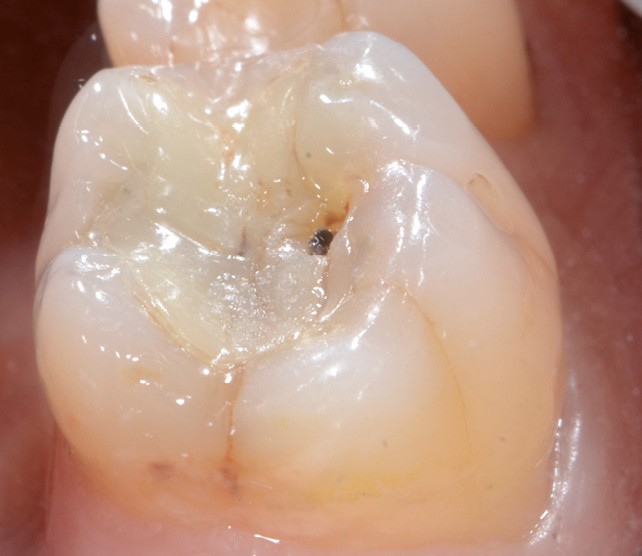

1 et 2. Un patient se présente à la consultation en raison d’une 36 douloureuse à la pression. La présence d’un inlay composite occluso-mésial ancien, infiltré, et des joints défectueux est constatée. L’analyse biomécanique révèle des fêlures, surtout au niveau de la crête marginale distale. Il faut de plus noter l’absence de la 37. Il est donc décidé de déposer la restauration et de réaliser un overlay en vitrocéramique de type e.max (Ivoclar Vivadent).

La fracture de la restauration (d’autant plus si le contexte occlusal est défavorable) ou le vieillissement prématuré du joint sont souvent dus à un non-respect des règles de préparation en fonction du matériau utilisé. Il est donc nécessaire de contrôler efficacement la profondeur de pénétration de la fraise dans la dent pour laisser la place minimale requise au matériau de restauration et préserver au maximum les tissus dentaires. Il convient de plus de maximiser la préservation de l’émail périphérique, garant de…